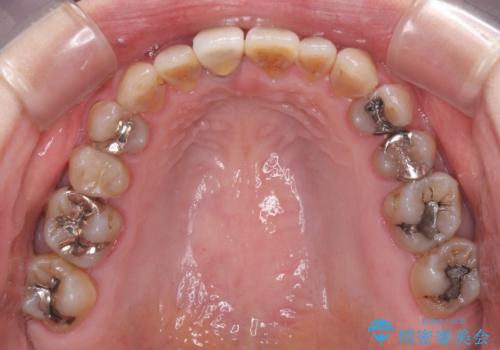

- 前歯のデコボコと、顎に負担のかかる歯並びを改善したいとのことで来院された患者様です。

うまく歯ぎしりができず、強く食いしばりをしてしまう咬み合わせであったため、奥歯に非常に負担がかかっていました。

インビザラインを用いて前歯のデコボコを改善するとともに、奥歯の咬み合わせを変えてスムーズに歯ぎしりできるように排列していくこととしました。